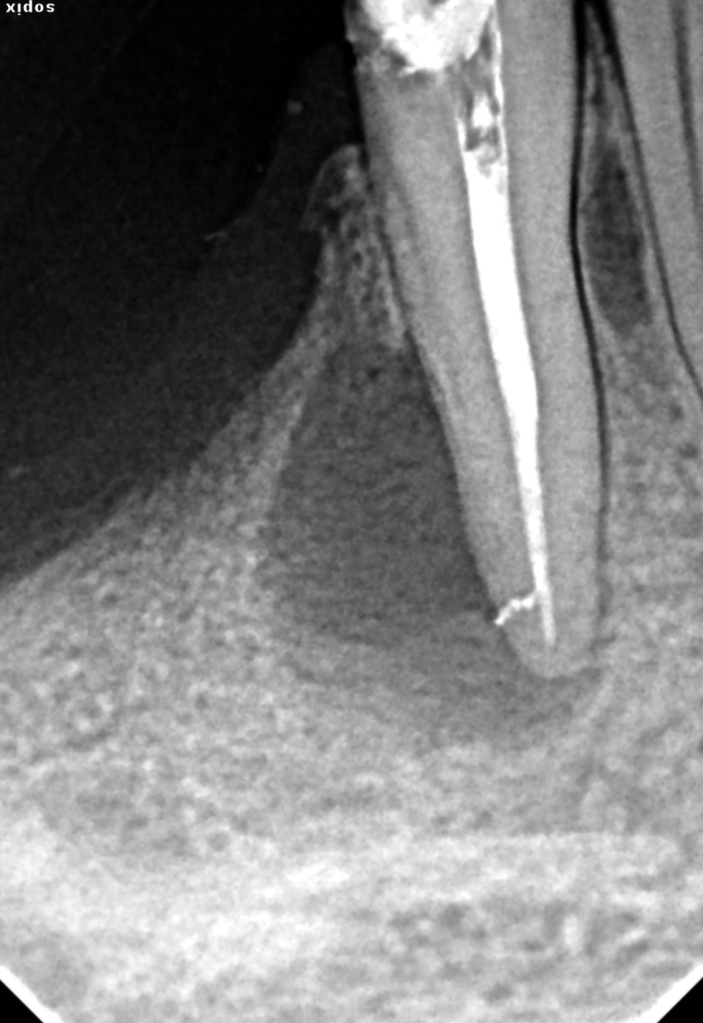

Retratamiento Lima Rota Apical